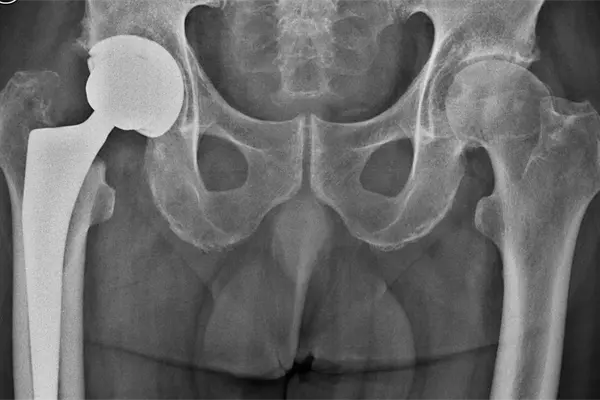

Cirugía inmediata tras fractura de cadera disminuye riesgo de muerte

Ciudad de México.- La fractura de cadera tiene una alta incidencia en personas mayores de 65 años de edad y constituye una de las principales causas de muerte en ese sector de la población.

Se calcula que la mitad de los pacientes muere en los seis meses posteriores a la lesión y gran parte de los sobrevivientes no recupera su nivel previo de independencia y funcionalidad, además de presentar afectaciones en cuanto a su equilibrio físico, mental, funcional y social.

Subrayan que la pronta solución quirúrgica disminuye la mortalidad por fractura de cadera y puntualizan que lo ideal es realizar la cirugía el día de ingreso al hospital o a más tardar un día después, siendo el principal obstáculo para ello la falta de disponibilidad de quirófanos o cirujanos.

También indican que entre más demore la cirugía el riesgo de complicaciones es mayor, siendo las principales: infecciones del tracto urinario, neumonías, tromboembolismo pulmonar, úlceras por presión y otros problemas cardiovasculares.

Los expertos detallan que 95 por ciento de los casos de fractura de cadera en pacientes mayores de 65 años son causados por una caída desde su altura.